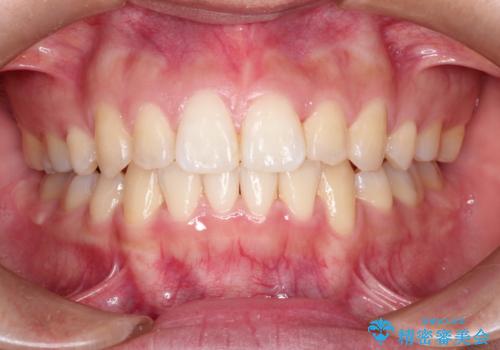

前歯が八重歯でガタガタ ワイヤーによる抜歯矯正